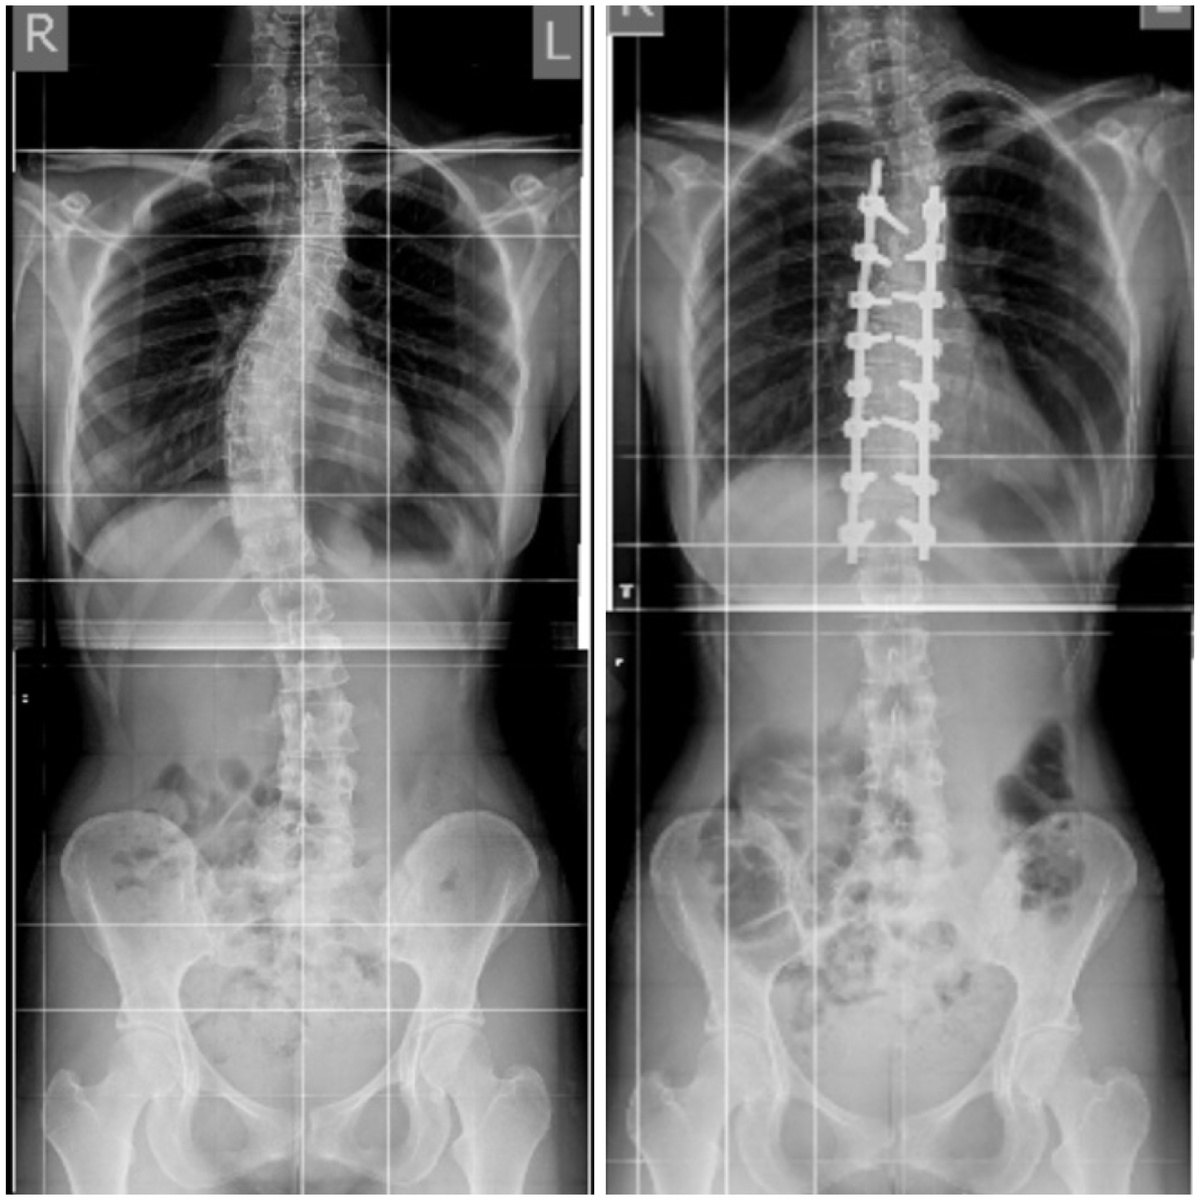

Сколиоз до операции. Основная дуга 45 градусов.

До и после коррекции сколиоза в больнице Вредена.

Спустя 11 месяцев от первой операции конструкция наклонились вбок, прогрессировала верхняя дуга. Справа результат после второй операции в клинике Пирогова.